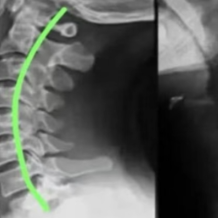

红网时刻新闻9月11日讯(通讯员 吴婷)“脖子像灌了铅,手麻得像过电,头痛得想撞墙”——这不是夸张,而是千万颈椎病患者的真实煎熬!骨科医生说“没到手术程度”,止痛药越吃越多却治标不治本,疼痛科正是为这类顽固性颈椎疼痛而生的“终结者”!

疼痛科视角:颈椎病为何痛得“花样百出”?